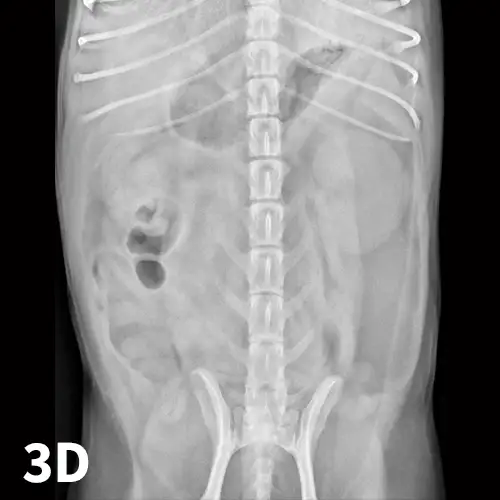

In cases of suspected FBs, this technique can be helpful to differentiate dilated small intestinal loops from colon or determine whether mottled mineralized material is in the colon or small intestinal tract. After initial survey radiographs are taken (Figures 6A and 6B), the animal is placed in lateral recumbency. Air is instilled into the rectum and colon using a large lubricated syringe or rubber catheter; approximately 10 to 12 mL/kg of air is needed for moderate distention of the colon.6,7 Standard lateral and ventrodorsal radiographs are then taken (Figures 6C and 6D). In most animals, it is desirable to fill the colon to the cecum. Partial filling of the distal jejunum and ileum may occur and is normal.

FIGURE 6A

Left lateral (A) and VD (B) survey radiographs of a 4-year-old pit bull terrier with a 3-day history of vomiting, diarrhea, and anorexia. A dilated loop of bowel is present within the midabdomen (star) caudal to the stomach, which could represent large or small bowel.